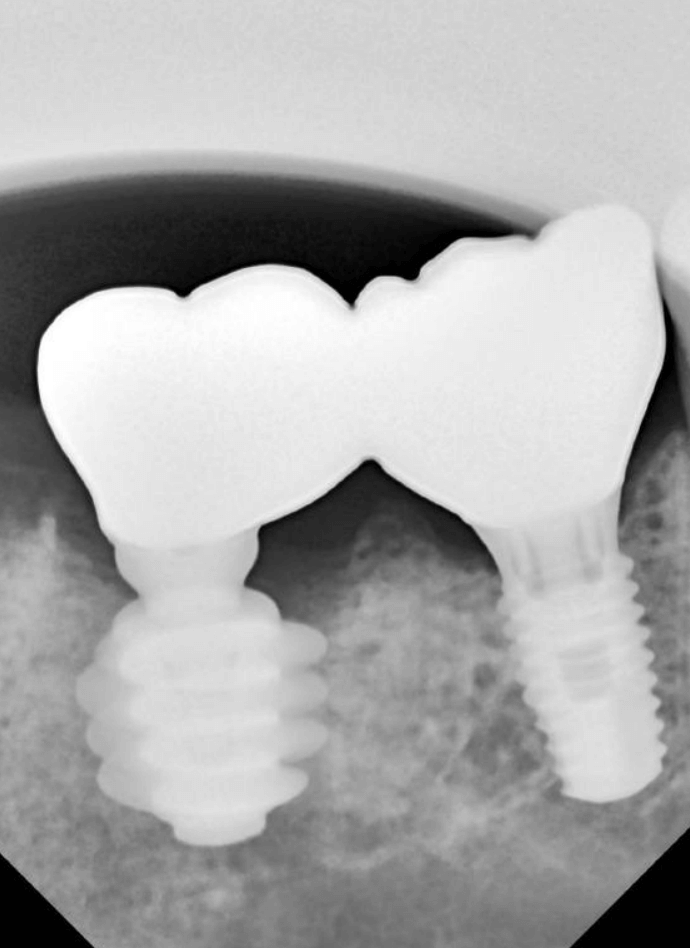

В область отсутствующей шестерки был установлен AnyOne Onestage Tussue Level, а в лунку моляра – широкий AnyRidge + мультиюнит с высотой десны 2,5 мм. Далее пластика мягких тканей.

Прекрасный результат через 3 месяца и постоянное протезирование сразу без временных реставраций.